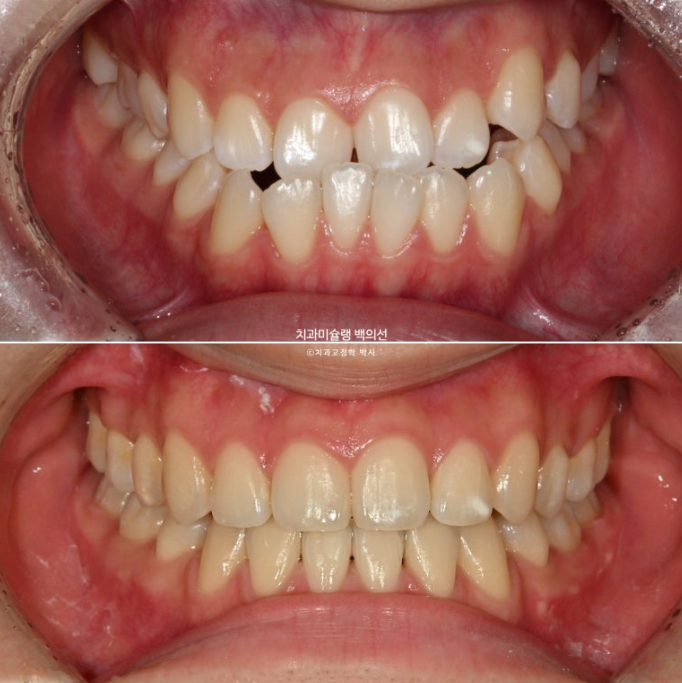

약 2년전, 교정치료를 위해 내원한 환자분입니다.

위아래 중심선이 서로 약 2mm가량 어긋나 있고 송곳니 덧니도 있습니다.

주걱턱으로 인해 앞니가 거꾸로 물립니다.

반대교합이라고 합니다.

골격성 주걱턱이라 양악수술이 필요한 상황인걸 알고 계시지만 양악수술까지는 원치 않았죠.

파란 화살표에 작은어금니가 하나 없습니다.

즉 결손치도 하나 있는 상태입니다.

만약 환자분이 작은어금니 하나가 없지 않았다면 비발치로 치료를 고려했을지도 모르나, 이미 없는 작은어금니에 균형을 맞추고자 나머지 작은어금니 3개 발치 계획을 세웠습니다.